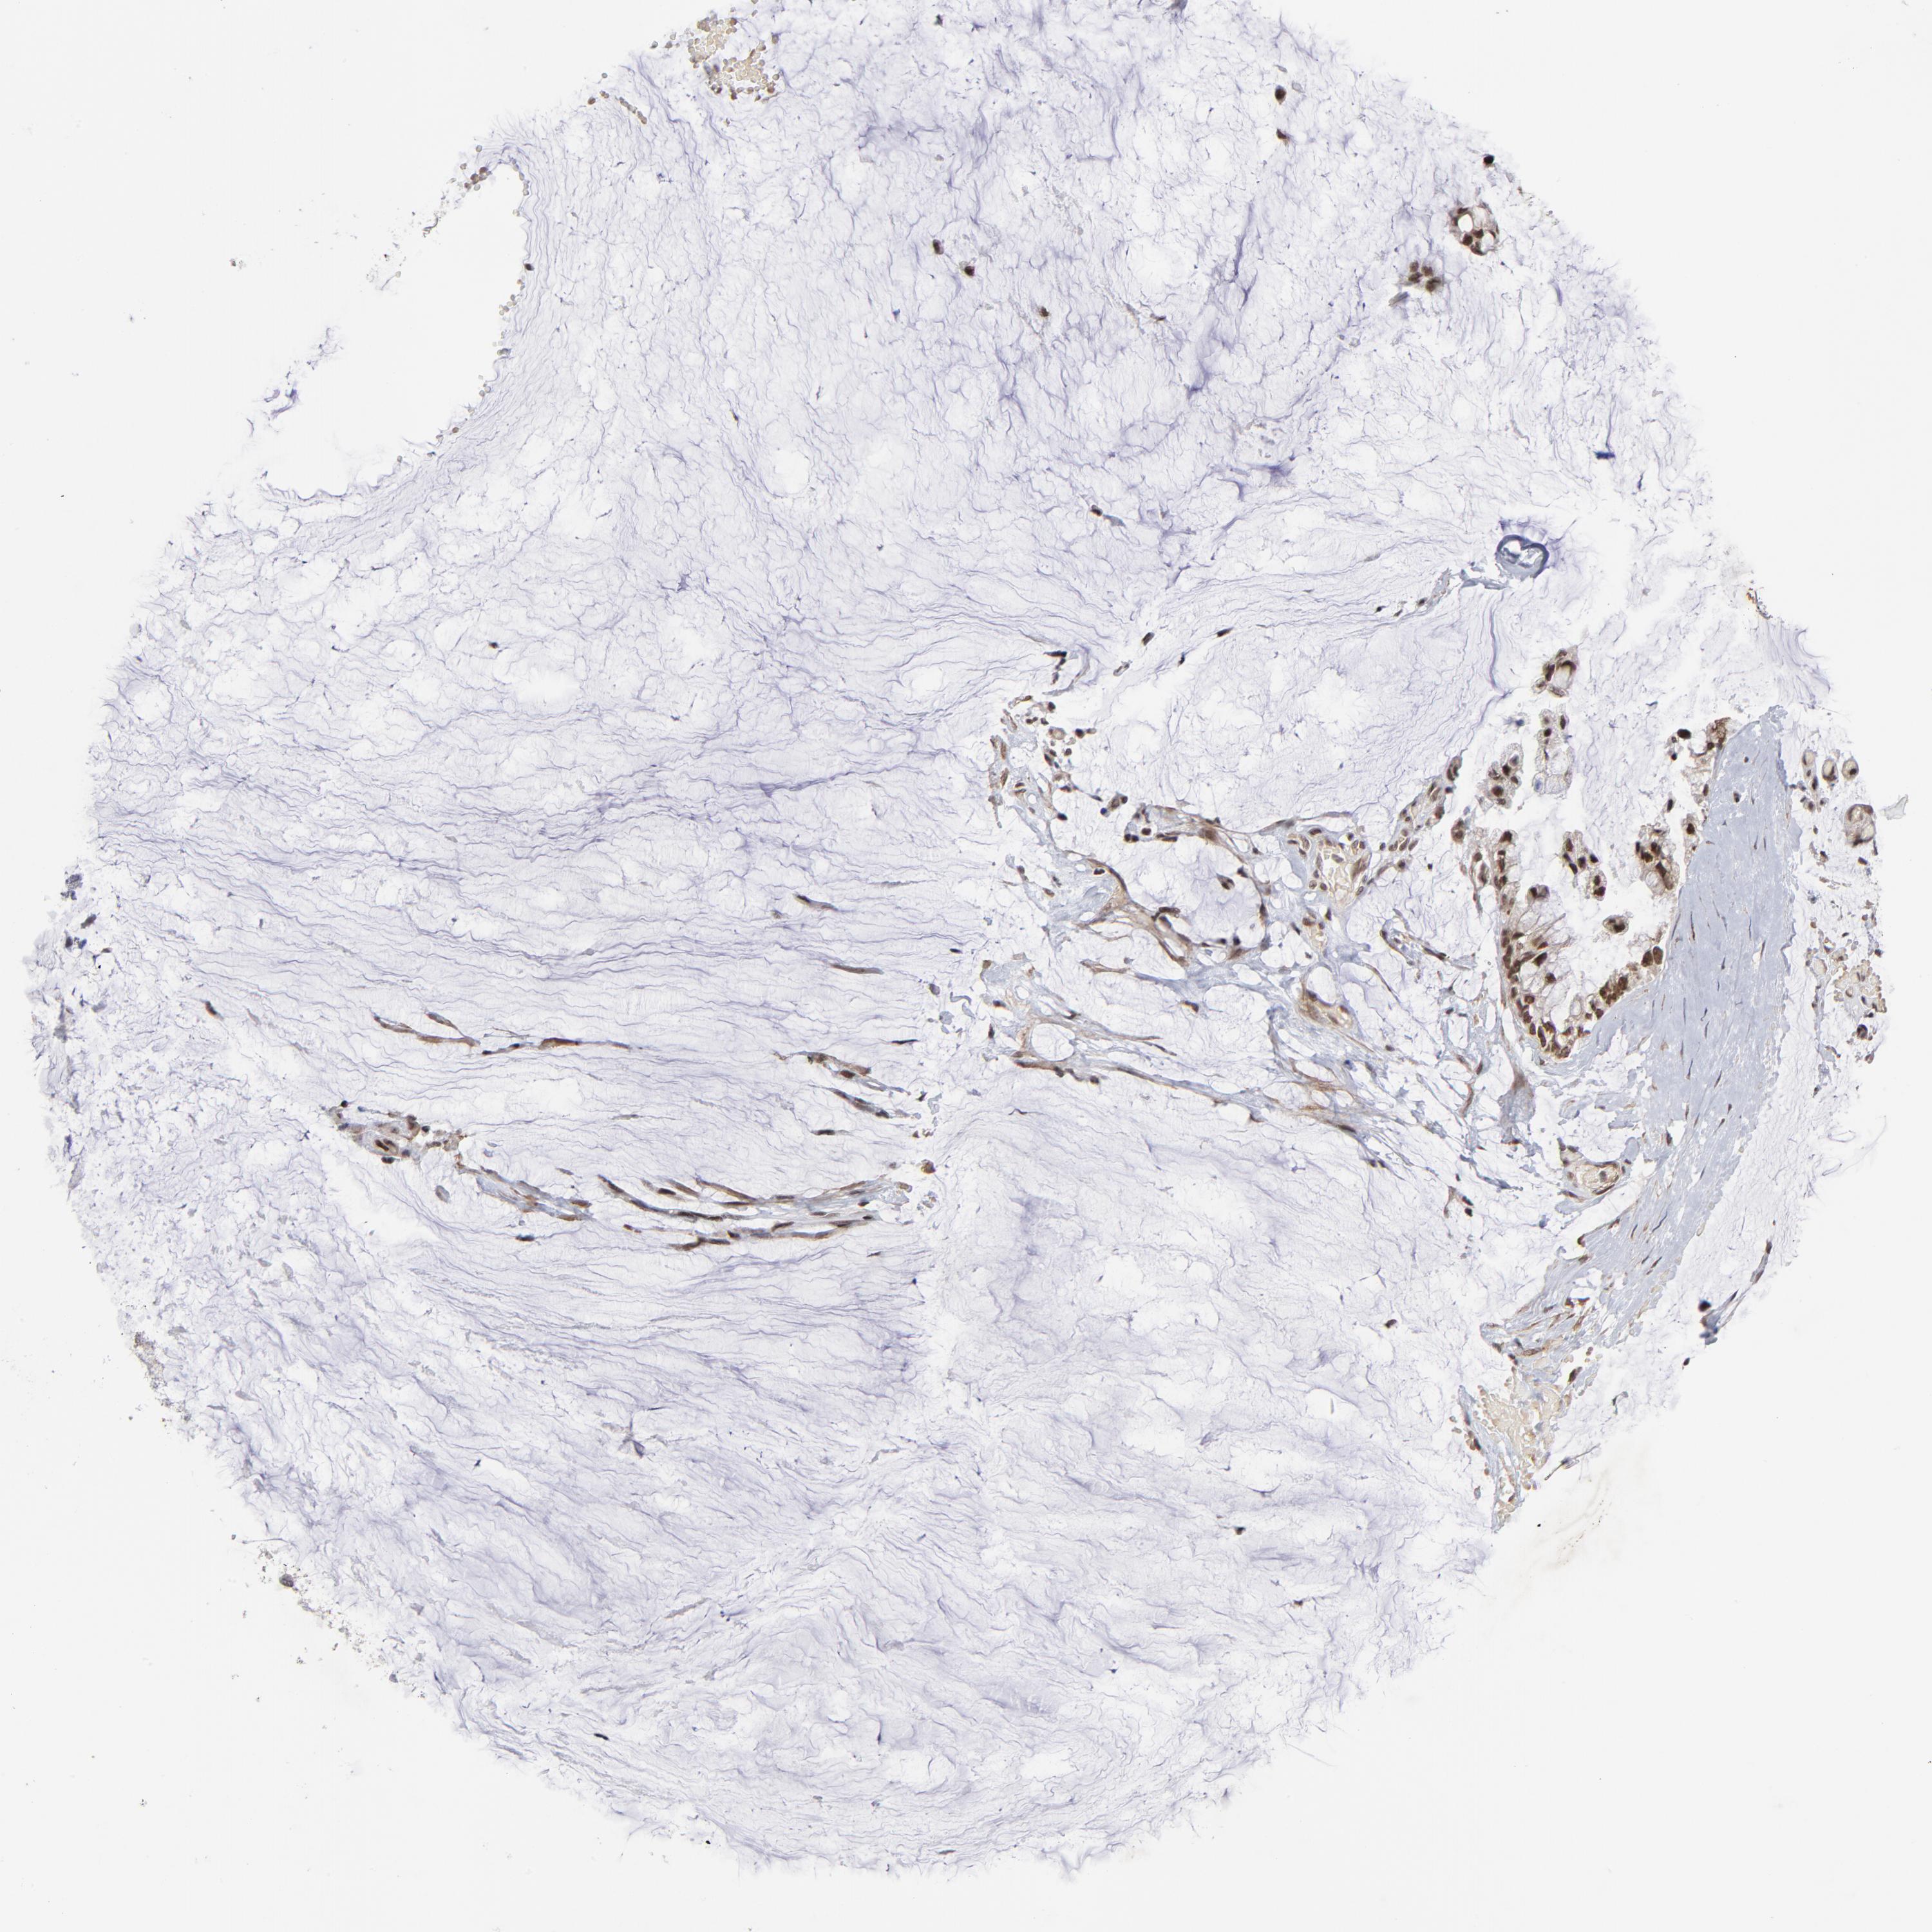

OVARIAN CANCER - Protein expressioni

A mouse-over function shows sample information and annotation data. Click on an image to view it in a full screen mode. Samples can be filtered based on level of antibody staining by selecting one or several of the following categories: high, medium, low and not detected. The assay and annotation is described here.

Note that samples used for immunohistochemistry by the Human Protein Atlas do not correspond to samples in the TCGA dataset.

Antibody stainingi

Antibody staining in the annotated cell types in the current human tissue is reported as not detected, low, medium, or high, based on conventional immunohistochemistry profiling in selected tissues. This score is based on the combination of the staining intensity and fraction of stained cells.

Each image is clickable and will lead to virtual microscopy that enables deeper exploration of all samples and also displays staining intensity scores, fraction scores and subcellular localization as well as patient and tissue information for each sample.

Antibody HPA004122

Antibody CAB062550

Antibody CAB068181

Antibody CAB068182

Staining

High

Medium

Low

Not detected

Intensity

Strong

Moderate

Weak

Negative

Quantity

>75%

75%-25%

<25%

None

Location

Nuclear

Cytoplasmic/membranous

Cytoplasmic/membranous,nuclear

Cystadenocarcinoma, serous, NOS

Cystadenocarcinoma, mucinous, NOS

Carcinoma, endometroid

Carcinoma, NOS

Adenocarcinoma, NOS